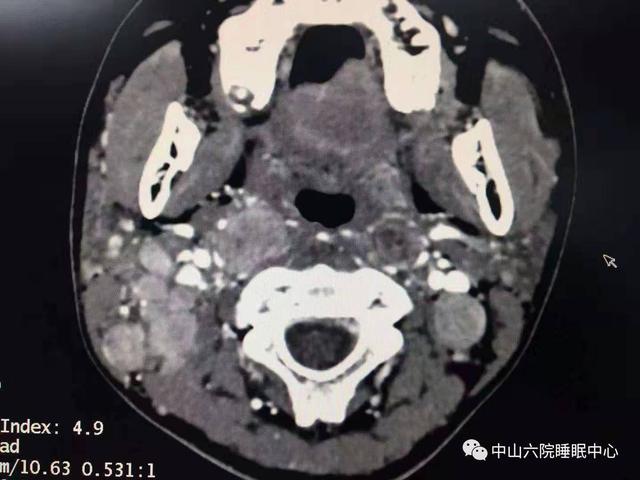

听了女孩的叙述,张湘民赶忙为她举行 了鼻内镜检查和联系CT增强扫描。鼻内镜检查效果 显示,患者右侧鼻咽可见重大 肿物,堵塞了后鼻孔且已经侵占 到左侧鼻咽部!

随后,病理陈诉确认了,女孩得的是“鼻炎未分化型非角化性癌”。增强CT显示,她的鼻咽部有重大 肿物,颈淋投合泛起多个转移病灶,癌症已经生长到了T3N3的晚期阶段。